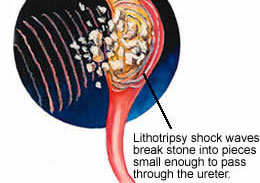

The lithotripsy is a medical process that shock waves used to treat stones in the kidney, ureter or bladder. A thin tube carries urine from kidneys to bladder. After this process the small pieces of the stones exits from our body through the urine.

Shock wave lithotripsy has two types technology. The original lithotripsy machines sent the shock wave through the water in a tube. In the tube patient being treated was placed. The mostly shock wave lithotripsy machine used by the specialist at the present time.